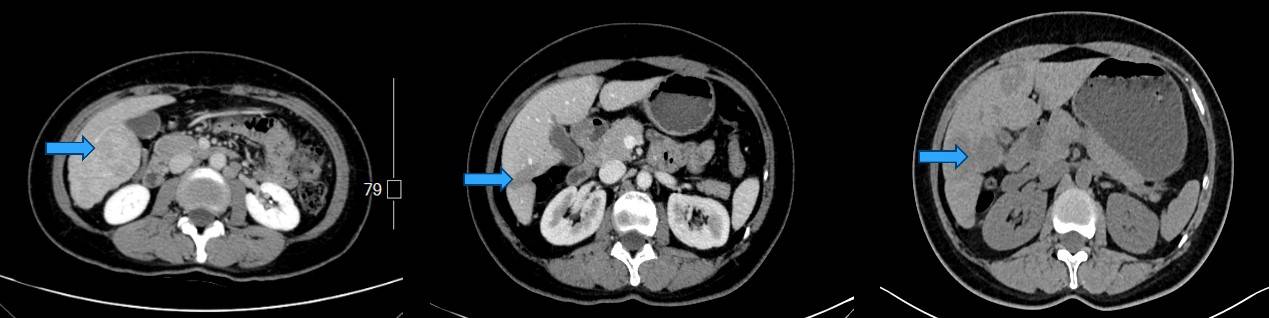

图4. 2018.8(左)2020.8(中)2022.4(右)上腹部CT对比病灶大小变化:7.5cm→3.8cm→4.6cm